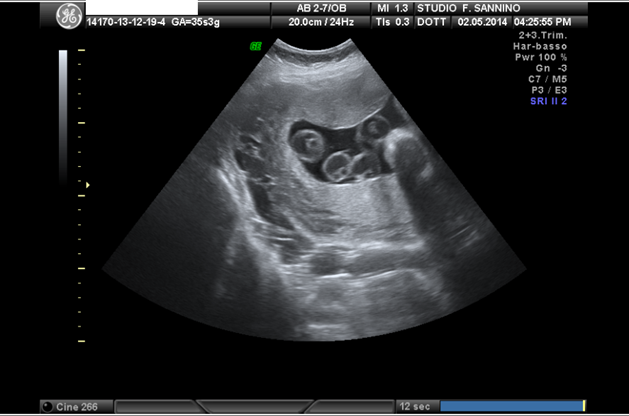

Alla 33,4 si evidenzia una dilatazione del tratto intraddominale ed extraepatico della vena ombelicale, 1,74 cm., che appare come una formazione cistica transonica disposta superiormente alla vescica. Al color doppler si evidenzia un flusso sanguigno continuo e regolare. Si effettuano ravvicinati controlli ecografici, flussimetrici e cardiotocografici. Risultano regolari la crescita fetale e la flussimetria sia sulle arterie ombelicali che cerebrali, non visualizzabile il dotto venoso di Aranzio.

33,4 settimane, si evidenzia una formazione cistica transonica, di forma allungata con diametro massimo di 1,74 cm., disposta superiormente alla vescica. Al color Doppler presenta un flusso sanguigno di tipo venoso regolare, assenza di turbolenze. Regolare la morfologia ecografica fetale.

La vena ombelicale intraddominale, presenta un tratto dilatato 1,39 cm. in vicinanza della parete addominale, a cui fa seguito un tratto normale fino al fegato. Regolare flussimetria venosa nel tratto aneurismatico. Regolare crescita fetale.

36,4 settimana, il Doppler venoso esprime una turbolenza, velocita 32,44 cm./sec